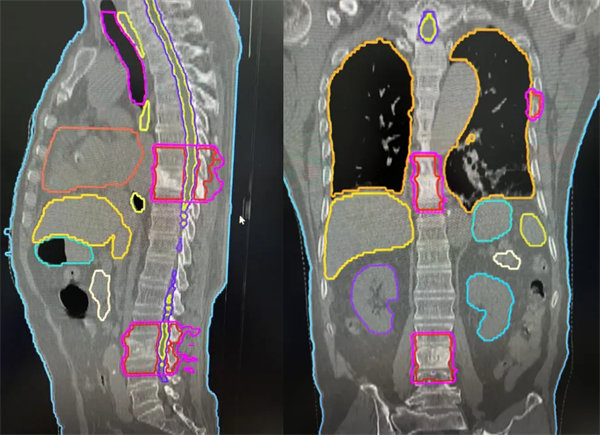

TOMO劑量分布均勻,適型度高

針對患者的病情,血液腫瘤風濕免疫內科副主任朱暉和放射治療科張世衡副主任醫師反復討論,最終確定長范圍、多病灶靶區的治療方案。由于患者及家屬對放射治療止痛效果的疑慮,科室反復多次和患者及家屬溝通:“張師傅,您放心吧,我們醫院的TOMO加速器是目前世界上最先進的放療機器之一,它的優點就是:TOMO有效治療范圍更大,最長可40CM*135CM,對于多發病灶可以在同一個定位區間內同時治療,正是TOMO這樣的特殊設計和功能,照射腫瘤的部位更精準、對周圍正常器官副作用小,而且每次治療之前都有CT圖像引導,可以根據病灶情況實時調整勾畫靶區,請您相信我們”。經過一番耐心地解釋說明,張師傅及家屬慢慢打消了顧慮,積極配合治療。在經過反復確認靶區、劑量及危及器官限值,科室討論后,一致認可此次放射治療的安全性和可實施性,放射治療科團隊加班加點,在兩天之內完成了制模,定位,靶區勾畫,計劃設計驗證,用最短的時間給張師傅安排了放射治療。血液腫瘤風濕免疫內科及放療主管醫生著重觀察患者對放療的反應,密切監測血常規、生化等指標,結合對癥支持治療,做好保駕護航。僅僅經過2次放療,張師傅腰背的癥狀就有了明顯的改善,晚上能安穩睡到天亮,直至5次放療結束患者未出現不可耐受的副作用。

肋骨、胸椎、腰椎轉移灶的長靶區照射(紅色區域)